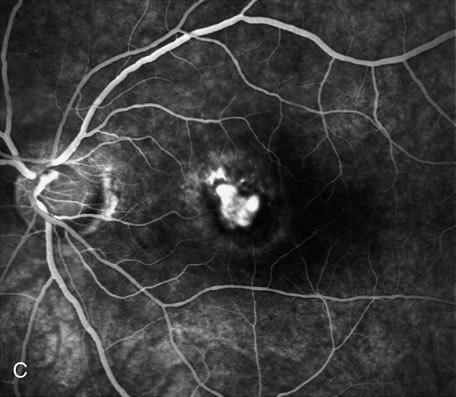

Furthermore, FA helps in recognizing two types of CNV: classic and occult. Classic CNV consists of a well-defined neovascular membrane, which is apparent in the early phase of the angiogram and shows late leakage of dye beyond its boundaries (Fig. 7 and 8). Occult CNV is seen on by FA as an area of late hyperfluorescence of undefined origin or as a neovascularized PED (Fig. 9 and 10 ). Mixed-type CNV is predominately classic or minimally classic depending on whether the classic component is more or less than 50% of the entire lesion (Fig. 11).

Fig. 9. A. Clinical photograph of the left eye of a patient with exudative neurosensory macular detachment. There were also intraretinal and subretinal hard exudates, subretinal hemorrhage, and retinal pigment epithelium (RPE) changes. B–D. Fluorescein angiography of the same eye demonstrates the presence of stippled hyperfluorescence from the RPE, and late-phase oozing of dye of undefined origin. There was occult choroidal neovascularization.

Fig. 10. A. Red-free photograph of the right eye of a patient with wet age-related macular degeneration. There was a large, exudative pigment epithelium detachment (PED), with a narrow band of subretinal hemorrhage at its inferior border. A notch in the PED is present at its nasal edge. There were also soft drusen. B–C. Fluorescein angiography demonstrates pooling of dye into the PED (short arrows). There was also late hyperfluorescence of undefined origin consistent with occult choroidal neovascularization (long arrows). There was blockage of fluorescence at the inferior border of the PED caused by subretinal hemorrhage.

Fig. 11. A. Red-free photograph of the right eye of a patient with wet age-related macular degeneration reveals exudative, neurosensory detachment in the macula and a few subretinal hemorrhages. B. Early-phase fluorescein angiography demonstrates well-defined classic choroidal neovascularization (CNV) (arrowhead). C. Late-phase fluorescein angiography shows leakage of dye from the classic CNV surrounded by an area of late hyperfluorescence consistent with occult CNV (arrows).